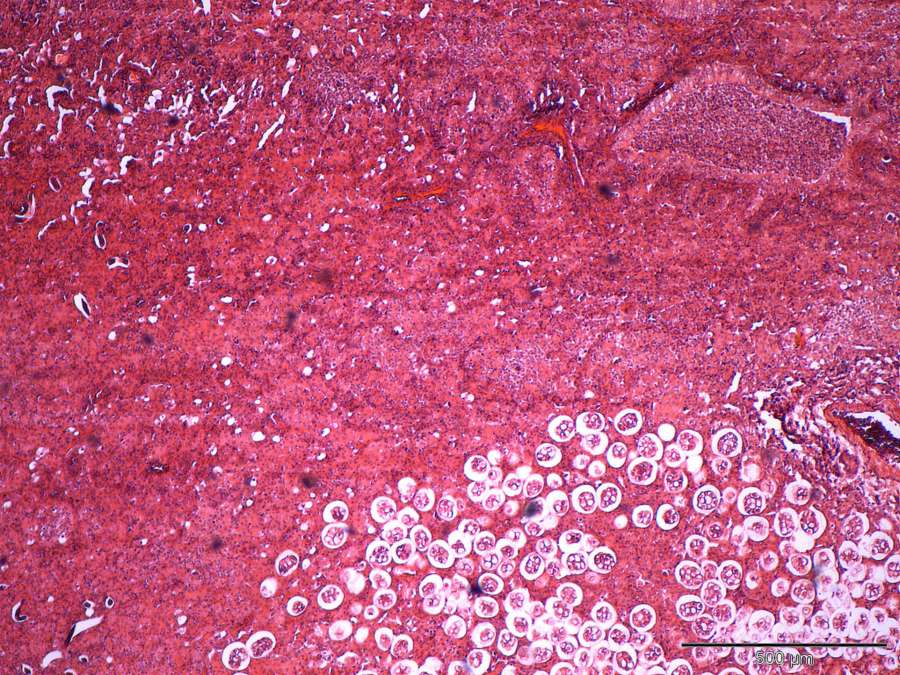

Diagnosis and management of lungworm infections in cats Cornerstones

from journals.sagepub.com